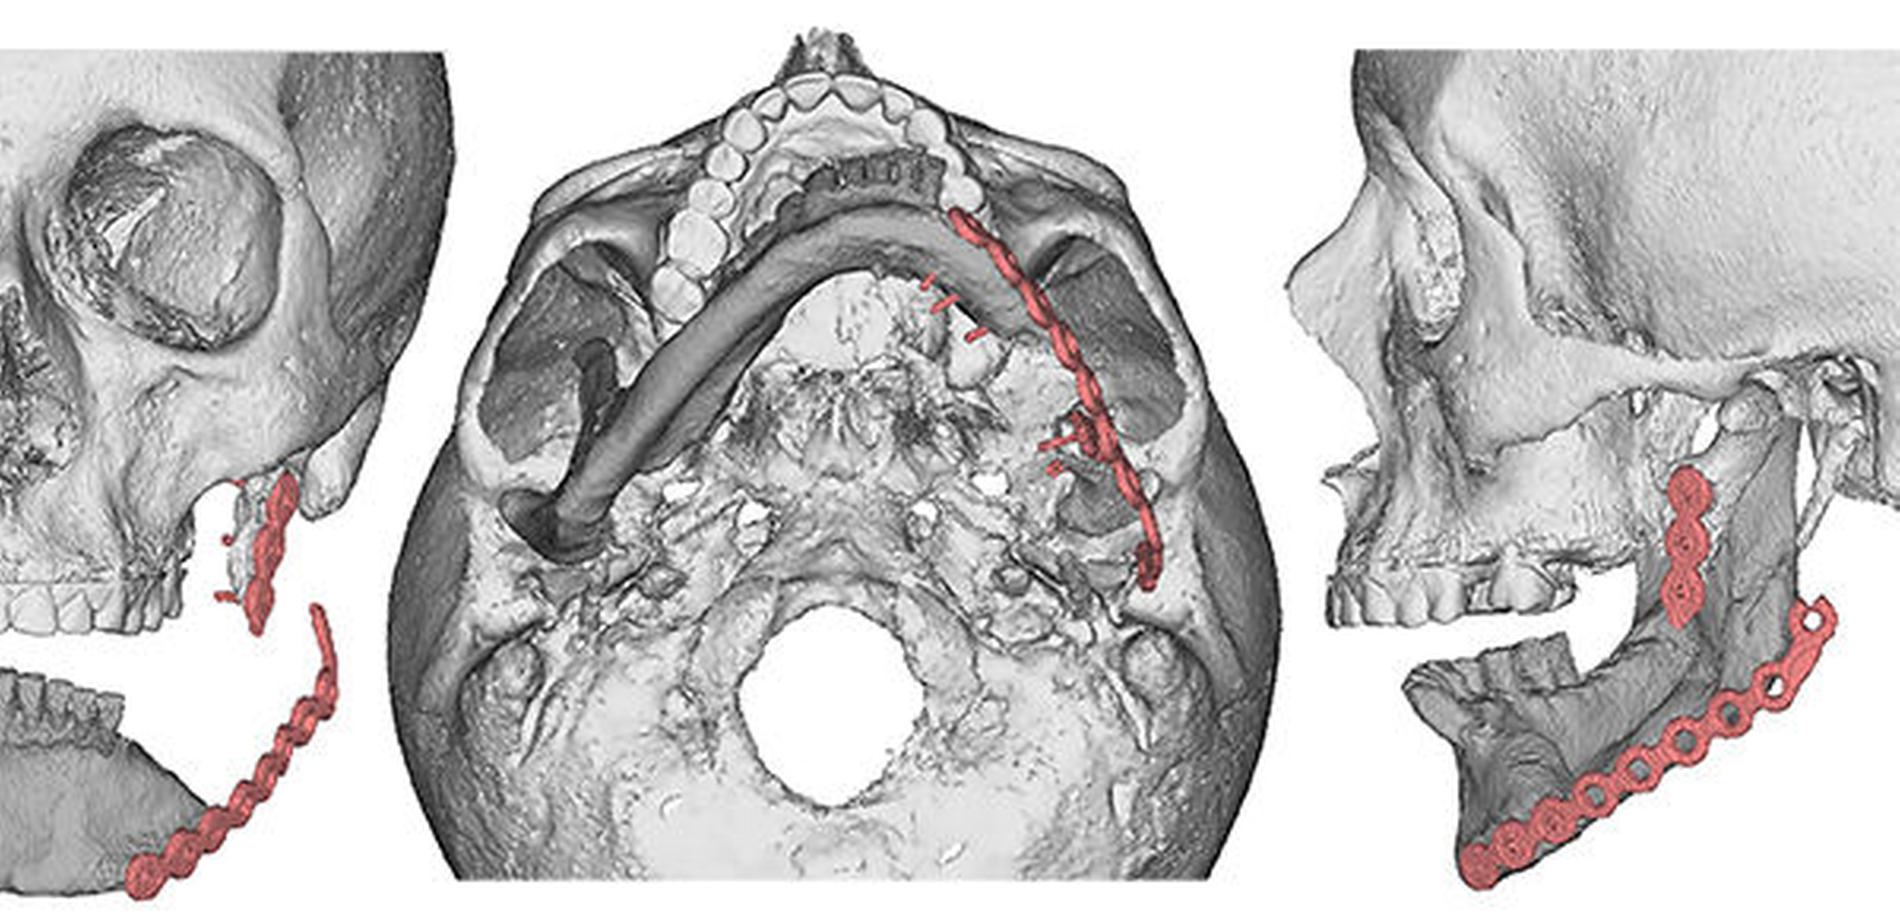

Hier findet weltweit am häufigsten das mikrochirurgisch reanastomisierte Fibulatransplantat für die Rekonstruktion Anwendung [Peled et al., 2005]. Durch die virtuelle präoperative Planung, Schneideschablonen - sogenannte cutting guides - und einem Patient Specific Implant (PSI) kann bei strikter Einhaltung der Protokolle ein exakteres Operationsergebnis erzielt werden [Hanken et al., 2015; Wilde et al., 2015].

Die CT-Daten wurde in die Software der Firma 3D Systems (3D Systems, Littleton, USA) eingelesen und aufbereitet. Dadurch ist es möglich, relevante Areale zu segmentieren und bei der Planung virtuell frei zu positionieren. Dies kann in Abbildung 3 gut nachverfolgt werden. Die rotierte Mandibula wurde in ihre ursprüngliche Position und somit die Restbezahnung in Okklusion mit dem Oberkiefer gebracht.

Die neue Okklusion wird postoperativ mittels intermaxillärem Splint gesichert (Abbildung 4). In den Folgeschritten werden die Resektionsgrenzen festgelegt und die notwendigen Fibulasegmente angepasst (Abbildung 5).

In Abbildung 8 sind die notwendigen Resektions- und Bohrschablonen dargestellt, die intraoperativ die Schnittgrenzen und Bohrlöcher festlegen.